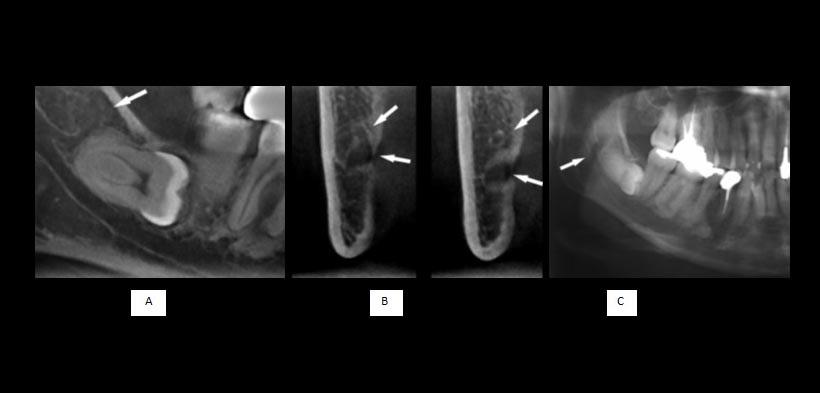

Fig 3. (A) imagen de la de la mandíbula derecha. (B) Imagen panorámica. La imagen de la tomografía (A) revela claramente un canal accesorio que surgió en la región retromolar y se unió al canal principal en la zona de la tercera molar (Tipo IV, flecha). El canal accesorio no se ve en (B) (flecha)